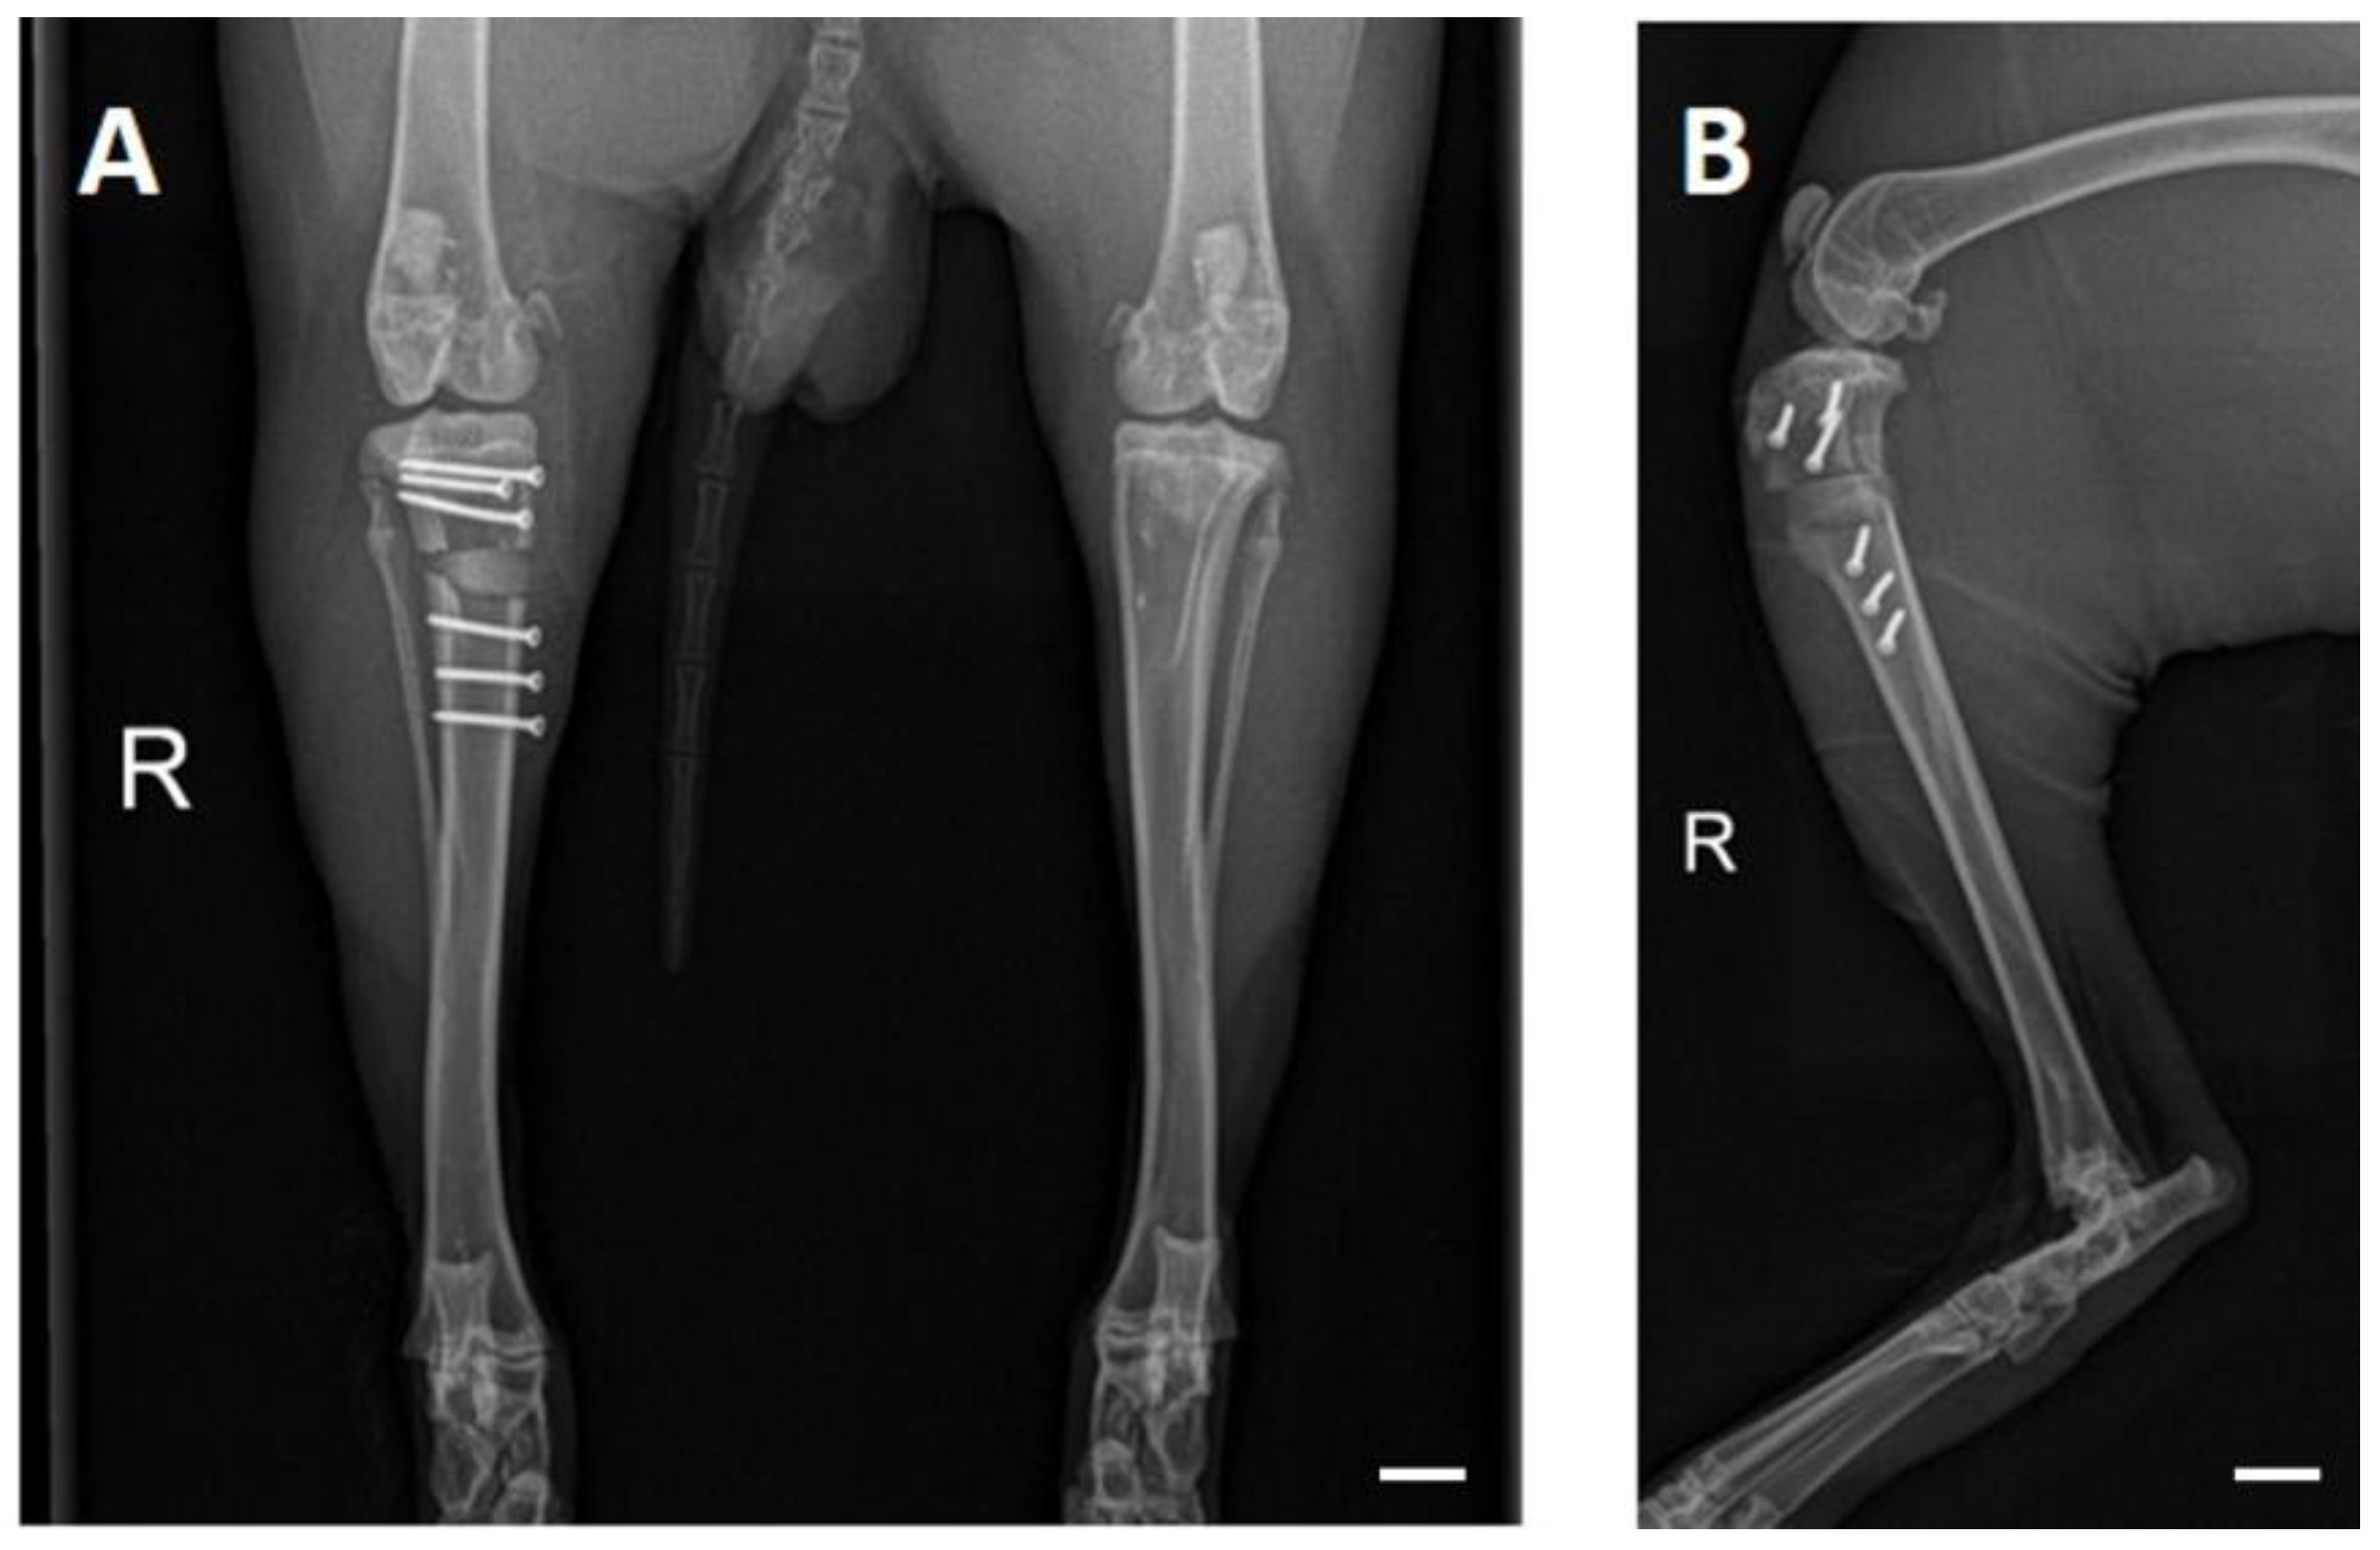

3.4. X-ray Examinations

3.3. OP and Clinical Examination